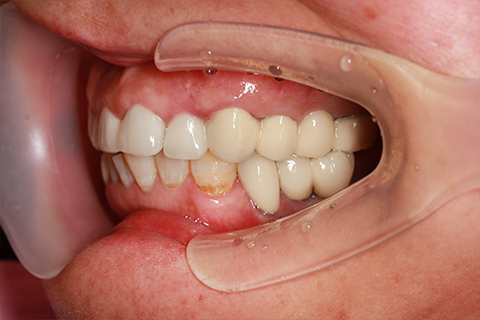

症例1

- 年齢・性別

- 55歳女性

- 治療期間

- 2ヶ月

- 抜歯

- なし

- 治療費

- 66万円

- 備考

- 右下6.7欠損

- 治療内容

- 右下6.7欠損部にインプラント埋入

- 施術の副作用(リスク)

- オペによる知覚障害。インプラントによる歯肉炎。インプラント脱落。